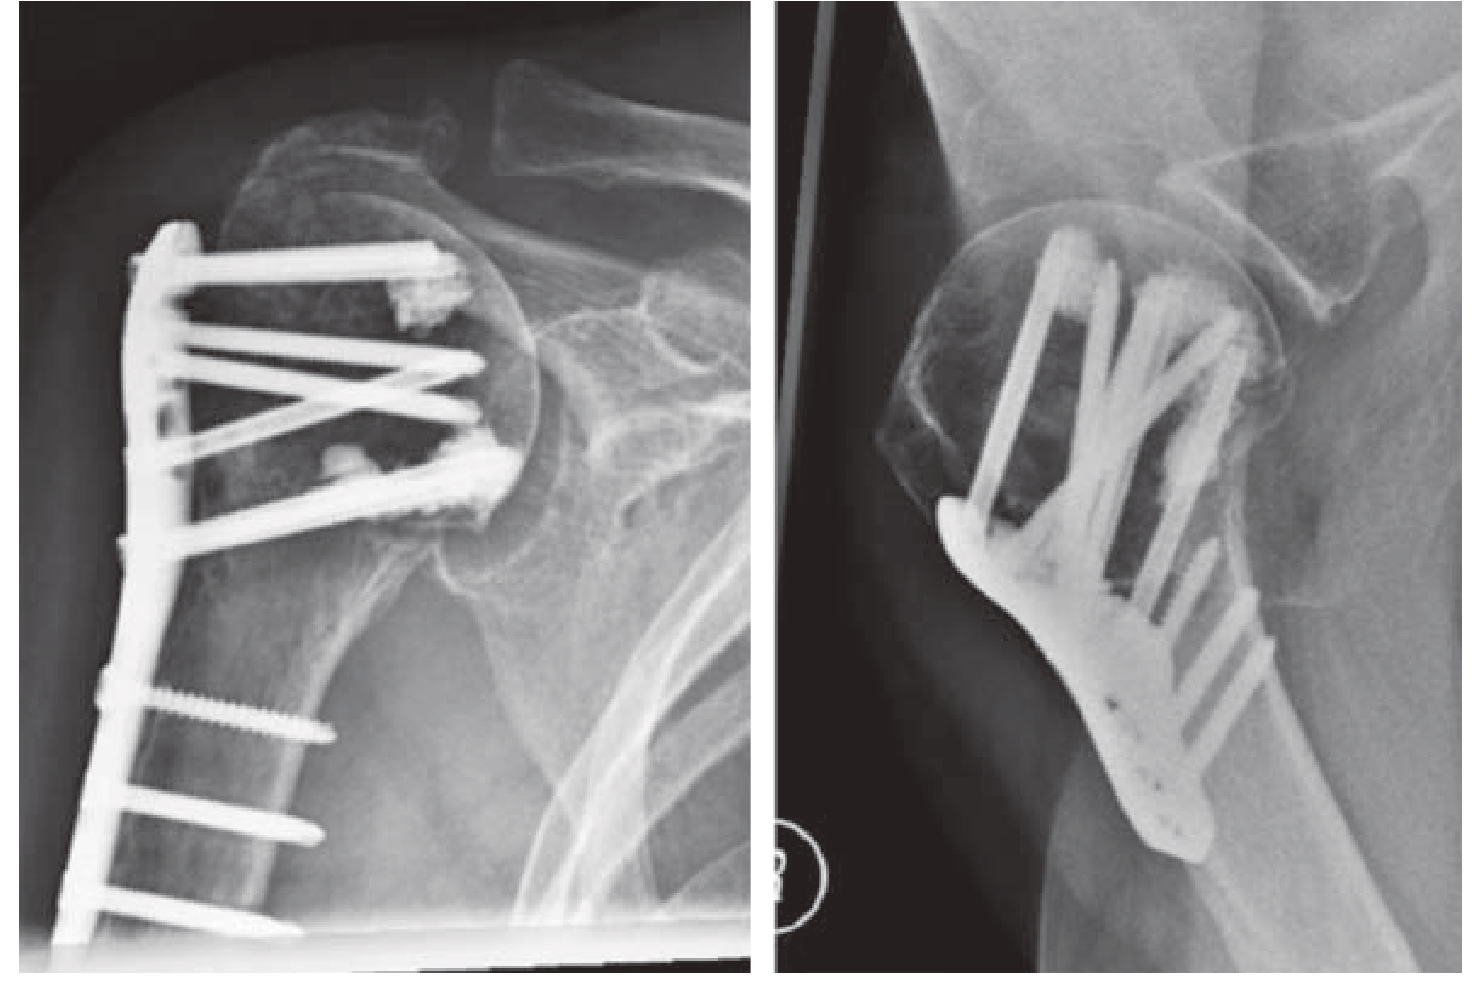

肩关节置换用于难以进行内固定或预计内固定失效风险大、效果不佳的患者。如部分肱骨头劈裂骨折;肱骨头压缩面积超过40%~50%的骨折;合并解剖颈骨折的三部分、四部分骨折—脱位;大小结节均骨折移位的外翻嵌插型骨折,且肱骨头外翻严重、内侧软组织铰链破裂、预计肱骨头缺血坏死风险大;高龄患者,严重骨质疏松及骨折严重粉碎的骨折[8,24]。以反式肩关节置换应用为主(图3—5),其次是半肩关节置换(肱骨头置换)(图3—6)。反式肩关节置换功能结果优于半肩关节置换[25,26]。对于老年人肩袖损伤、缺血严重且三角肌功能完好的肱骨近端三、四部分骨折建议反肩置换,而对于功能要求低、肩袖完整的肱骨近端三、四部分骨折患者,可以考虑半肩置换。

img

图3—5 83岁女性,肱骨近端四部分骨折脱位,严重骨质疏松,行反式肩关节置换

图3—6 半肩关节置换治疗肱骨近端四部分骨折[27]